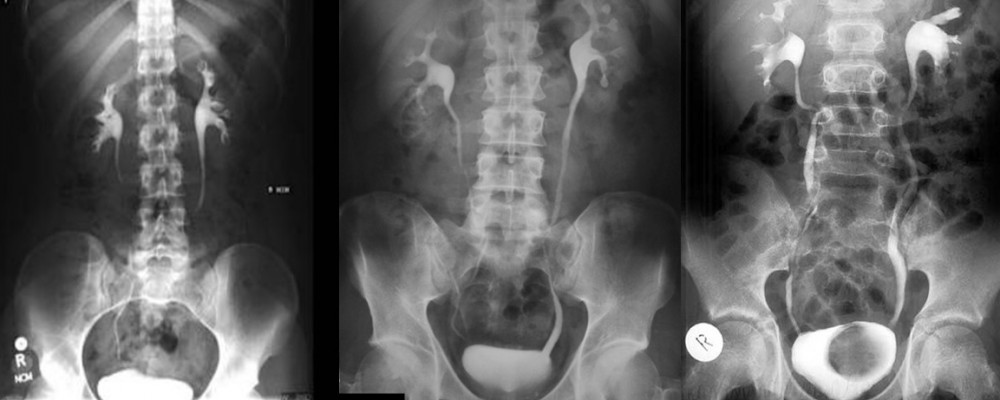

Böbrek taşlarının %90’ı radyoopaktır ve DÜSG’ görülürler .DÜSG’de yalnız ürik asit ve ksantin taşları görülmez. Bunlar da İVU’de dolum defektleri şeklinde görülürler. Direk üriner sistem grafisinin (böbrek, üreter, mesane radyogram.Sol yan ağrısı şikayeti olan hastaya çekilen intravenöz pyelografinin, direkt üriner sistem filminde L2-L3 vertebra hizasında sağda 1×1 cm ve sağda 2×5 cm boyutlarında, yine sağ pelvis içindeki 5mm’lik opasitenin görünen opasitelerin, piyelogram fazında

böbrek anatomisiyle olan ilişkisi görülmektedir. Ancak hastaya non-kontrast bilgisayarlı tomografi çekilecekse DÜSG çekilmesi gereksiz olduğundan önerilmemektedir